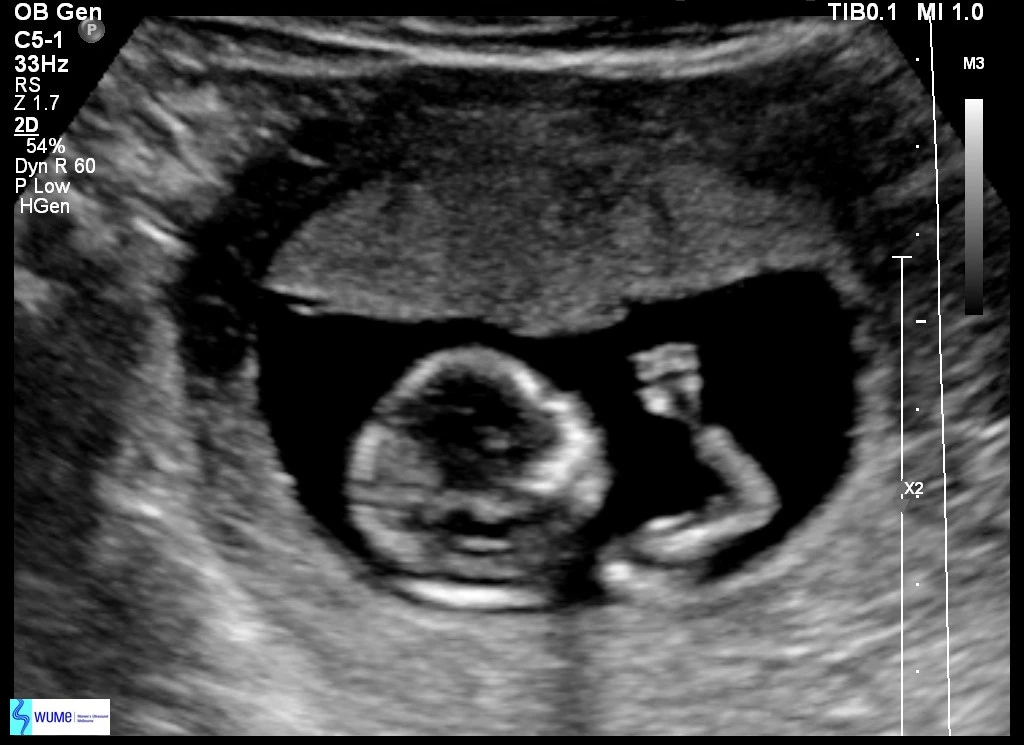

13주 2일

너에게 쓰는 편지가 이제 정말 너라고 부를 수 있는 네가 나에게 왔구나 싶다. 오늘 긴 팔다리와 손가락 발가락까지 있는 너를 보고 왔어. 다행히 시아버님의 코를 닮지 않은 오뚝한 코까지 보여 얼마나 안심했는지 몰라. 심장소리도 너무 크고 움직임도 너무 좋고 다 너무 좋았어. 초음파를 보러 가기 전 불안한 마음은 어쩔 수 없나 봐. 건강한 너를 보니 마음이 노여 병원을 다니오니 긴장이 풀리더라.